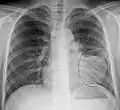

Normal AP CXR

AP CXR showing left lower lobe pneumonia associated with a small left sided pleural effusion

AP CXR showing right lower lobe pneumonia

AP CXR showing pneumonia of the lingula of the left lung

Right upper lobe pneumonia as marked by the circle.

Left upper lobe pneumonia with a small pleural effusion.

Right lower lobe pneumonia as seen on a lateral CXR